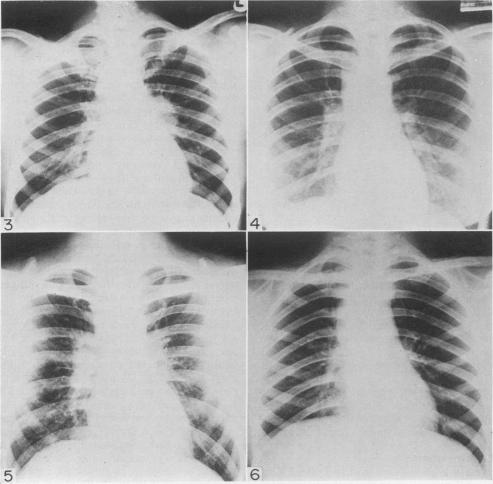

Mediastinoscopy: a diagnostic procedure in hilar and paratracheal lymphadenopathy.

Postgrad Med J. 1971 Nov;47(553):698-704. doi: 10.1136/pgmj.47.553.698.

Mediastinoscopy, in the skilled hands of a thoracic surgeon, is a safe, cosmetically accepted procedure with negligible complications, less than that reported in many series of scalene node biopsies. It has the advantage of yielding a much higher rate of diagnostic tissue, in all instances over 90%. In the cases of tuberculosis it enabled an organism to be isolated and sensitivities obtained. It has also revealed a group of cases with findings, a further study of which may increase our understanding, assessment and management of patients presenting with hilar and/or paratracheal lymphadenopathy.